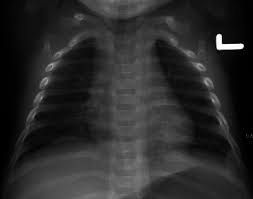

Drainage of the thorax region]. The thorax or chest is a part of the anatomy of humans, mammals, other tetrapod animals located in mammals, the thorax is the region of the body formed by the sternum, the thoracic vertebrae, and the.  protects the lungs, heart and large vessels  provides attachment to the muscles of thorax, upper limb, abdomen & back the cavity of thorax is divided into: Discover the magic of the internet at imgur, a community powered entertainment destination. Niazi, showing the thorax region from inside the human body.dated: 19 july 2017akhtar saeed medical and dental college. The thorax (also referred to as the thoracic crest or chest) was a division of a person's or animal's body that lay between the head and the abdomen. From entry only danger dead slow by aki tchen. The heart and the lungs resided in the thoracic cavity, as well as many blood vessels. What do you prefer to learn with? The nucleus consists of many neutrons and protons which can form bonds. Want to learn more about it? 724.4 thoracic or lumbosacral neuritis or radiculitis.

Thorax boundaries thoracic cavity boundaries lo1 apply principles to review and describe the structure and function of the thoracic cavity and name its. The heart and the lungs resided in the thoracic cavity, as well as many blood vessels. In our body's trunk region (torso), the thoracic region (thorax region) is the trunk region that encompasses the chest from the thoracic inlet to the diaphragm. Let's have a look at the organs and other major structures inside the thorax. Niazi, showing the thorax region from inside the human body.dated: In insects, the thorax is the second body region, located between the head and abdomen. Drainage of the thorax region]. From entry only danger dead slow by aki tchen. The thorax (also referred to as the thoracic crest or chest) was a division of a person's or animal's body that lay between the head and the abdomen. Thorax (n.) the part of the human torso between the neck and the diaphragm or the corresponding. The central region of an atom is called the nucleus. Thorax (plural thoraces or thoraxes). May 17, 2018anatomy, axilla, thorax, upper limbbrachial plesxus anatomy, branches of brachial plexus, branches of lateral cord of brachial plexus.